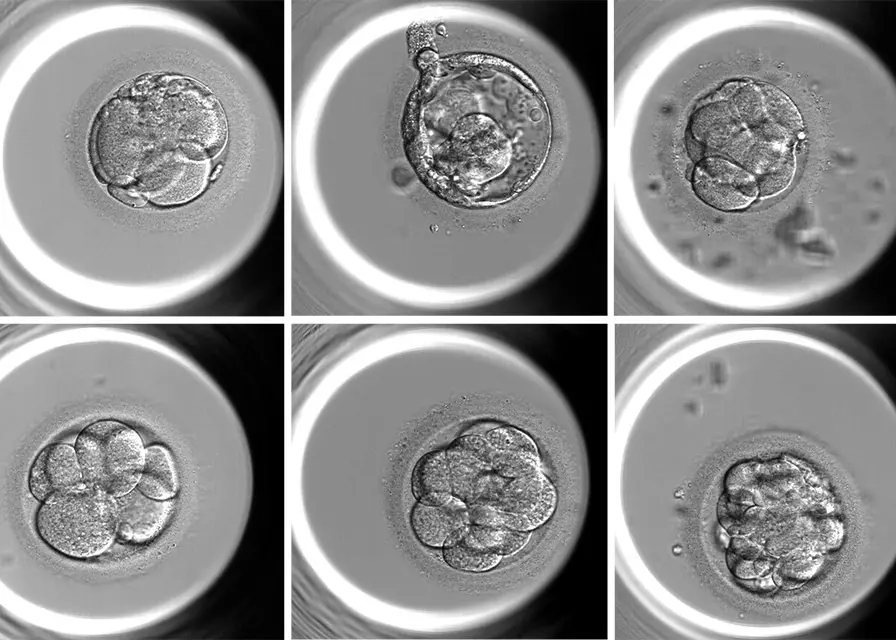

Las herramientas VIOLET™, MAGENTA™ y ROSE™ se basan en un modelo predictivo que evalúa la probabilidad de que un óvulo alcance el estadio de blastocisto, etapa clave en el desarrollo embrionario. Cada sistema está orientado a una instancia específica del tratamiento: VIOLET™ para pacientes que congelan óvulos, MAGENTA™ para ciclos de fecundación in vitro (FIV), y ROSE™ para procesos de donación ovocitaria.

“La calidad y el potencial de cada óvulo pueden medirse con mayor precisión, lo que permite planificar mejor los tratamientos y reducir los tiempos de espera”, señaló Marconetto. Además, estas herramientas aportan transparencia y respaldo en la toma de decisiones tanto para profesionales como para pacientes.